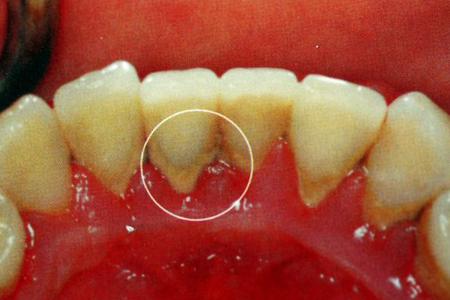

前下牙齿内侧根部掉了一小块是怎么回事?_妈

下门牙齿里面掉了一块,这是怎么回事?有图